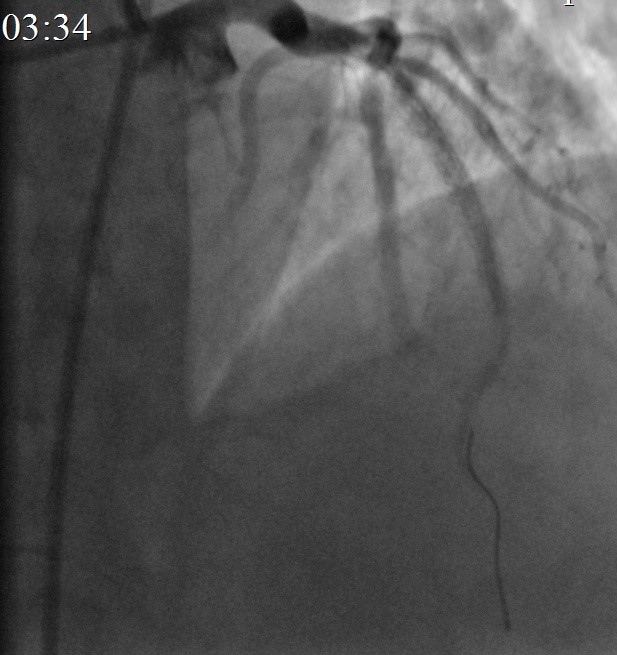

На КАГ: ПМЖА – устье кальцинированный стеноз 50%, среднем отделе кальцинированный протяженный стеноз 99% с переходом в кальцинированную окклюзию, дистальный кровоток TIMI 0-I. (в последующем наблюдается спонтанная реканализация перед ЧКВ, с кровотоком TIMI II-III). Дистальные отделы заполняются фрагментарно ретроградно из ветвей ПКА. ПКА проксимальном отделе стеноз 40%.

Контрольная КАГ: просвет ПМЖА в зоне вмешательства полностью восстановлен, остаточный жесткий кальцинированный стеноз среднего отдела стентированного сегмента 50%, антеградный кровоток TIMI III на протяжении по всем артериям.